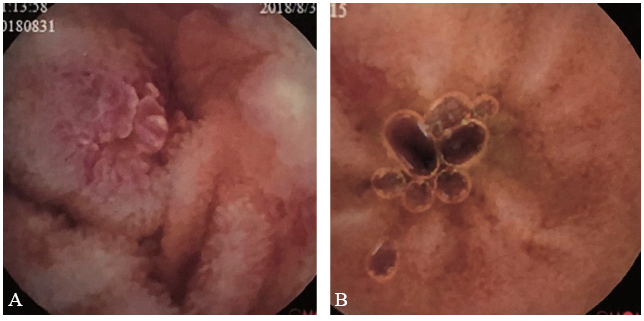

图4 一例EG患者治疗前后胶囊内镜对比图

A:治疗前胶囊内镜显示小肠各段多发散在糜烂溃疡;B:治疗后胶囊内镜显示小肠溃疡明显好转,以瘢痕期为主

X线胸片提示双肺未见异常。胃镜检查显示胃底、胃体、胃窦及十二指肠仍有多发散在溃疡,直径约0.5 ~ 0.8 cm(图1A、B),病理活组织检查(活检)提示胃黏膜呈慢性活动性炎症,固有层较多嗜酸性粒细胞浸润,约60个/高倍镜视野(图2A)。结肠镜显示回肠末段、升结肠、横结肠、乙状结肠及直肠局部黏膜充血、水肿,多发散在点、片状糜烂及溃疡,直径约0.1 ~ 1.0 cm,病变间隔有正常黏膜(图3A、B)。病理活检提示肠黏膜呈慢性活动性炎症,固有层较多嗜酸性粒细胞浸润,其中回盲部约100个/高倍镜视野,结肠约60个/高倍镜视野(图2B、C)。胶囊内镜显示小肠黏膜多发散在糜烂、溃疡灶,溃疡形状不规则,直径约0.3 ~ 0.8 cm,病变呈跳跃性,病变之间有正常黏膜(图4A)。

全腹部增强CT提示肠系膜周围见多发肿大淋巴结,未见“靶征”“木梳征”等征象。综合病史、临床表现及上述检查结果,拟诊为EG,给予口服泼尼松15 mg,每日2次。1周后患者腹痛症状显著改善,复查嗜酸性粒细胞绝对值0.01×109/L,嗜酸性粒细胞百分比1.1%。患者出院后继续口服糖皮质激素维持治疗。4个月后患者复诊时腹痛症状基本缓解,复查胃镜(图1C、D)、结肠镜(图3C、D)及胶囊内镜(图4B)均显示消化道溃疡大部分愈合,溃疡数量较前明显减少,病变范围较前明显缩小。半年后随访患者已停用糖皮质激素,腹痛等症状未复发,食欲及大便情况也较前明显改善。最后诊断:EG。